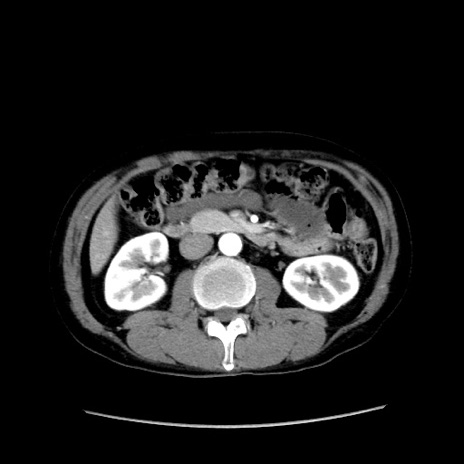

症例37(横断像)

【症例】40歳代 男性

【主訴】腹痛

【現病歴】4時間ほど前に電車に乗車中に臍部上より腹痛出現。徐々に増悪し起立困難となり、救急外来受診。生ものは数日食べていない。今朝お雑煮を食べた。

【身体所見】BT 36.8℃、BP 117/84mmHg、HR 91/min、SpO2 97%、苦悶様、腹部:臍上部広範囲圧痛あり、反跳痛±

【データ】WBC 8100、CRP 0.03